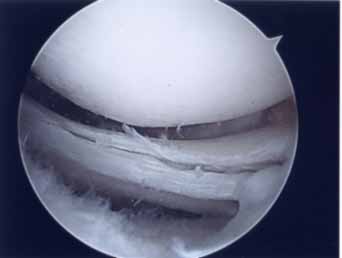

半月板部分切除術

半月板の手術は関節鏡下部分切除術が中心です。関節鏡を入れる1cm弱の傷と半月板を切除するパンチを挿入する別の1cm弱の傷の2カ所でほとんど出来ます。手術翌日に松葉杖なしで退院出来ます。関節鏡下部分切除術317例の10年以上の調査でも中高齢者の変性断裂は症状が続く場合には手術的に治されることがベターです。手術成績に影響する因子として、35歳以上の年齢、軟骨変性所見、半月後方1/3切除例、半月rim切除例などを指摘する論文もあります(Chantain 2001)。従来は後節1/3を切除することが多かったのですが、できるだけ痛みに関係する部分のみ切除する小部分切除法 (limited small resection) を現在では行っています。

(水平断裂合併)

(水平断裂は僅かに残存)

正常に見えるが